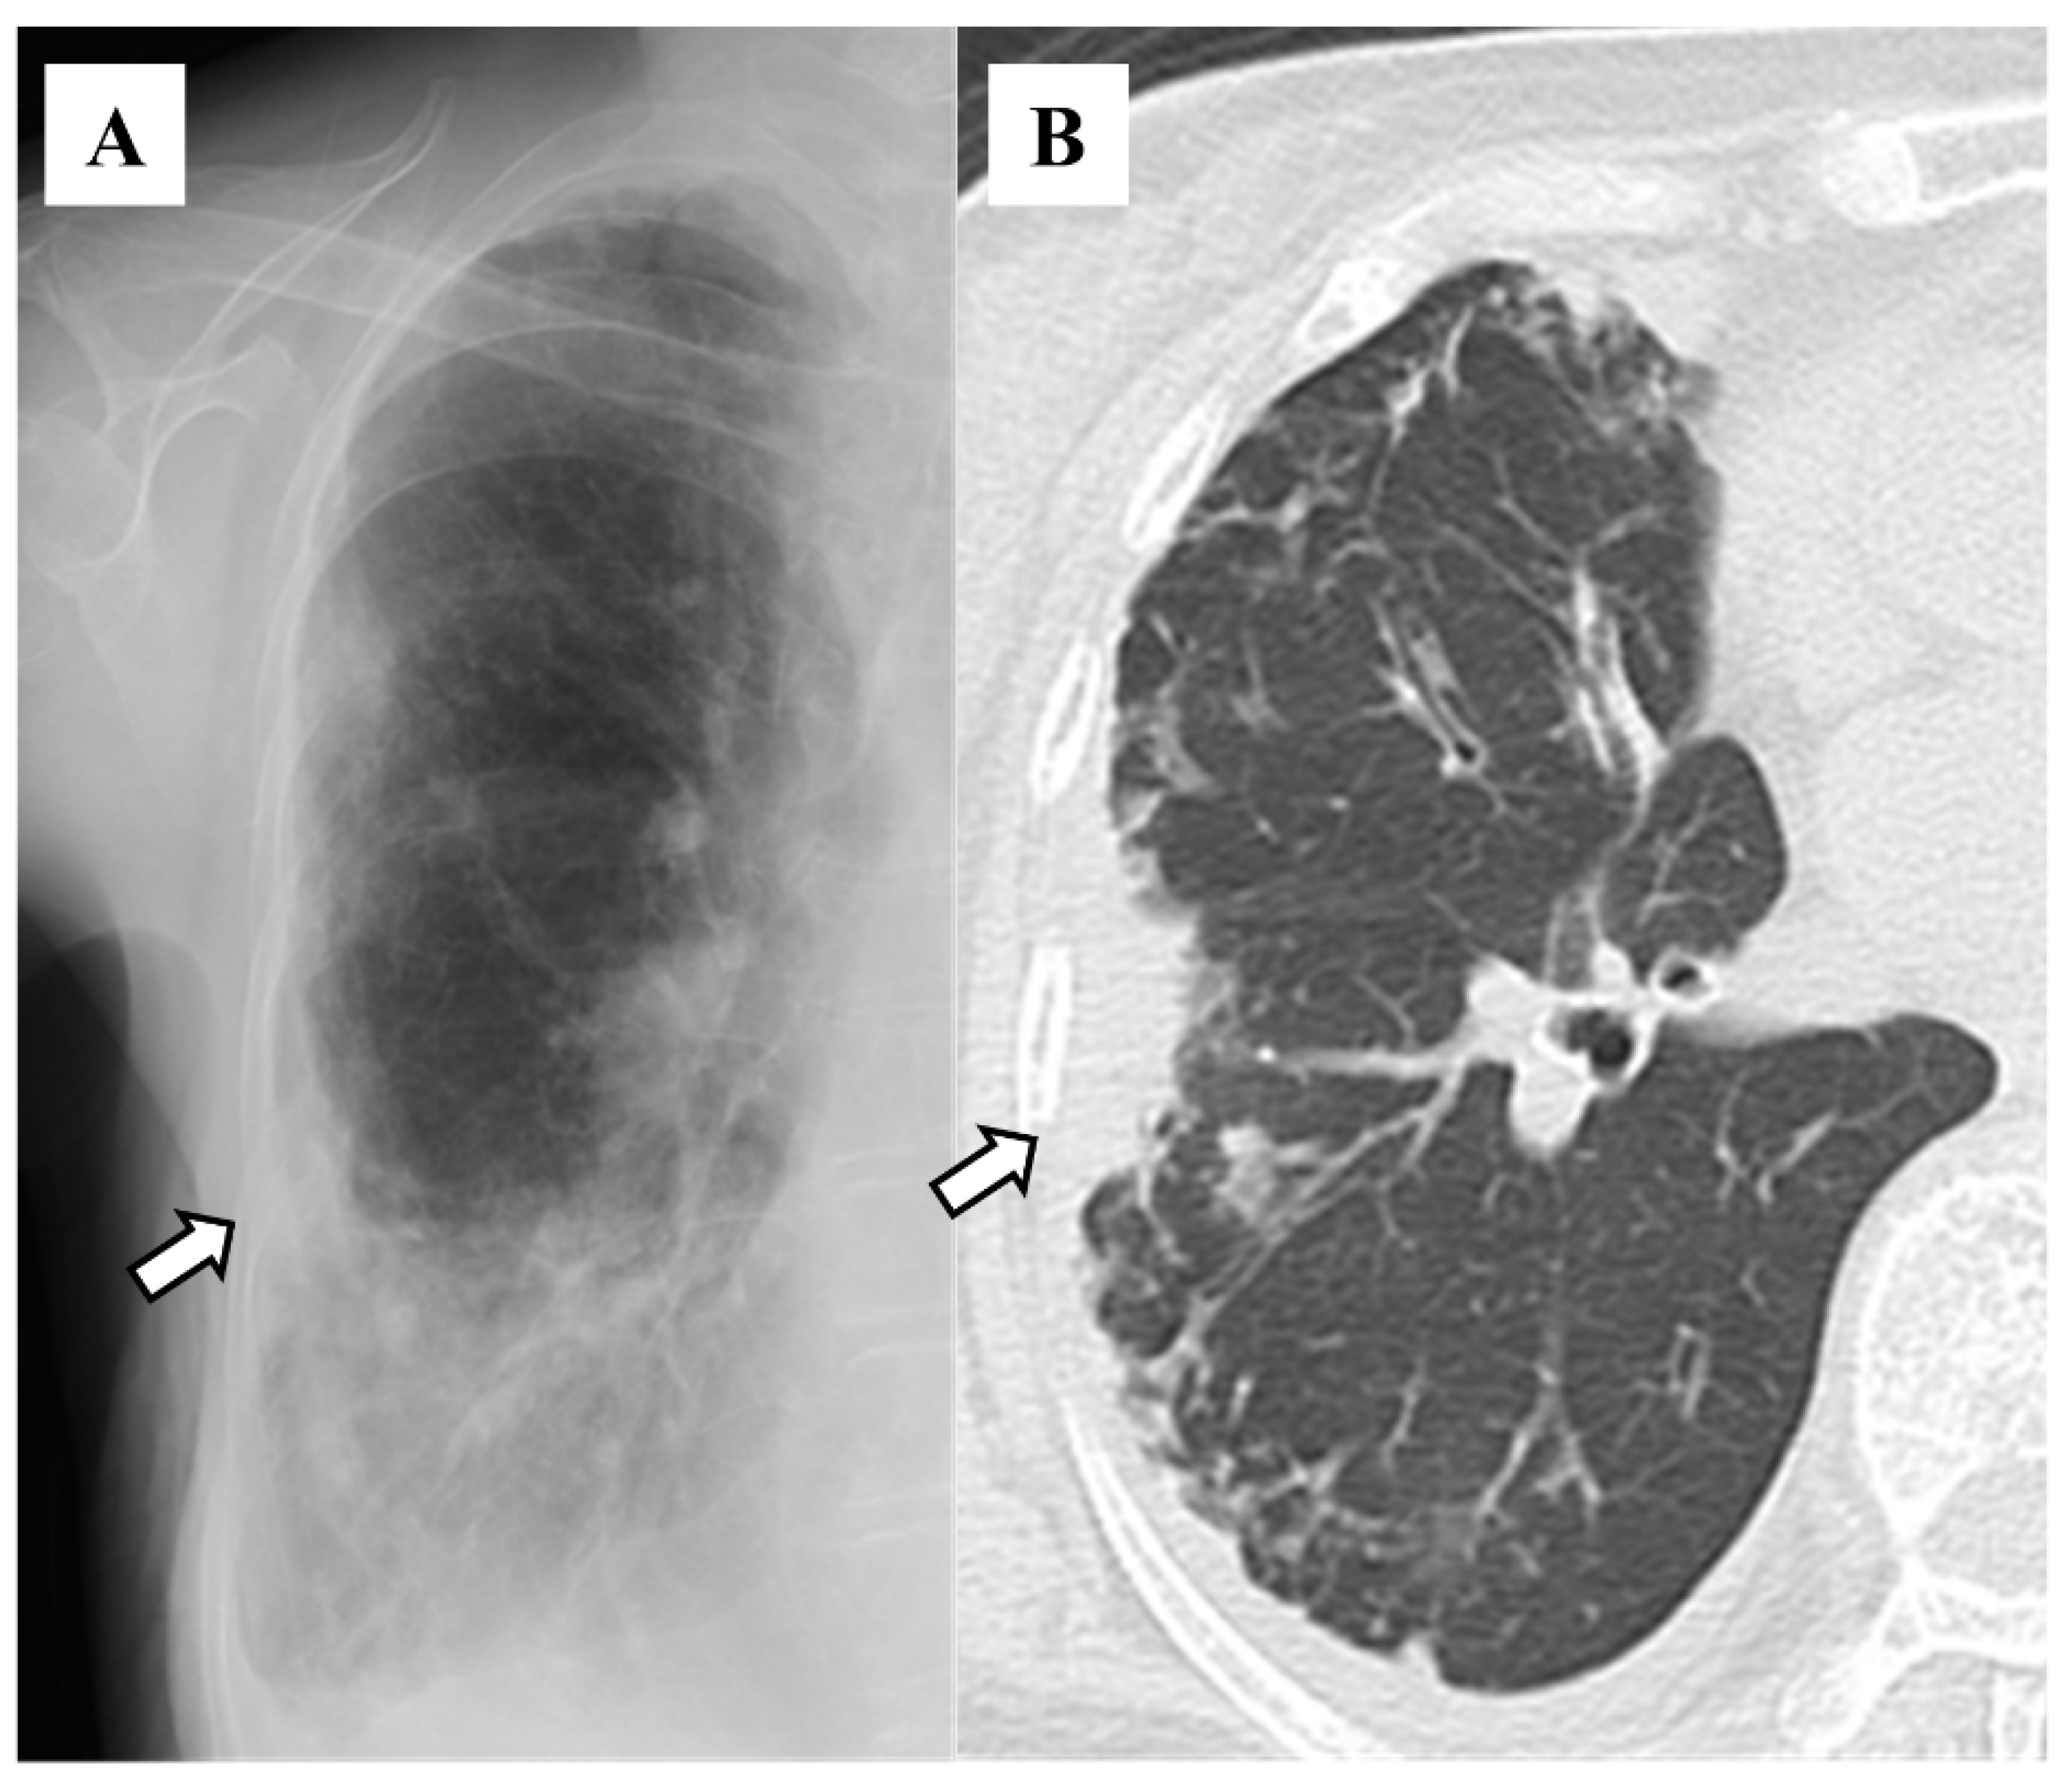

| Air–fluid level | 5 (3.8) |

| Atelectasis | 8 (6.2) |